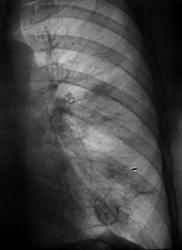

Рентгенограммы и их фрагменты.

Ниже представлены прицельные рентгенограммы пищевода, произведенные в процессе исследования данного пациента, в ортоположении водной взвесью сернокислого бария обычной консистенции.

Ниже рентгенограммы, произведенные на трохоскопе с применением сметанообразной и пастообразной контрастной взвеси.